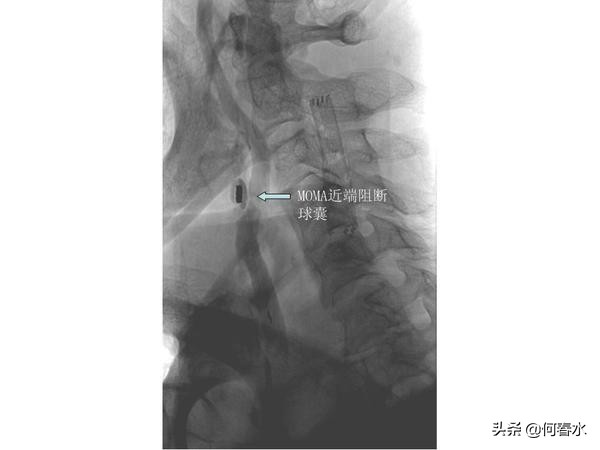

右侧颈动脉重度狭窄且伴有溃疡,若采用保护伞类远端保护装置极有可能在通过保护伞的时候将狭窄处的血栓或斑块碰落引起脑梗塞,所以我们采用最先进的近端保护装置—MOMA阻断球囊技术,有效提高了手术的安全性。